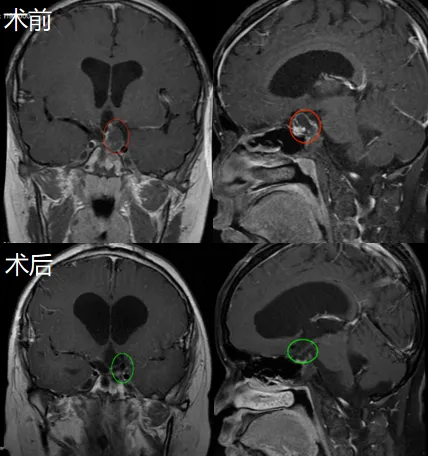

不久后,小圭一家前往德国接受手术治疗。巴特朗菲教授成功为他实施手术,在术中磁共振成像系统及术中神经导航的辅助下,肿瘤获得全切,且垂体柄得到最大程度保护。术后第二天,小圭即转出ICU,左眼视力未受新的损伤,神志完全清醒,对答流利。术后近半年MRI复查显示,无肿瘤进展及复发征象。